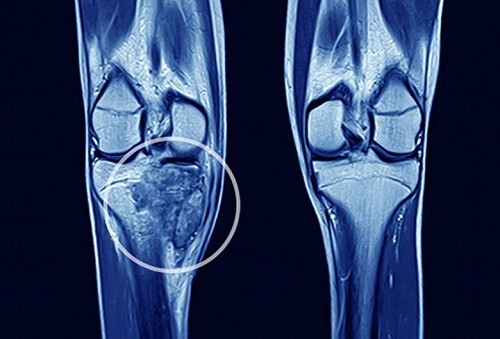

Ung thư xương

Ung thư xương phát triển tại vùng bị va đập hoặc gãy xương